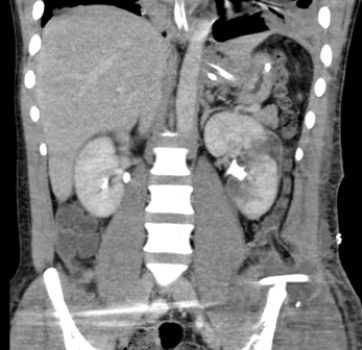

This enhanced CT image is consistent with:A) a history of painless obstructive jaundice.

B) a patient with colicky left flank pain suspicious for ureteral calculus.

C) a trauma patient with a lacerated kidney.

D) an alcoholic with cirrhosis.

a trauma patient with a lacerated kidney.